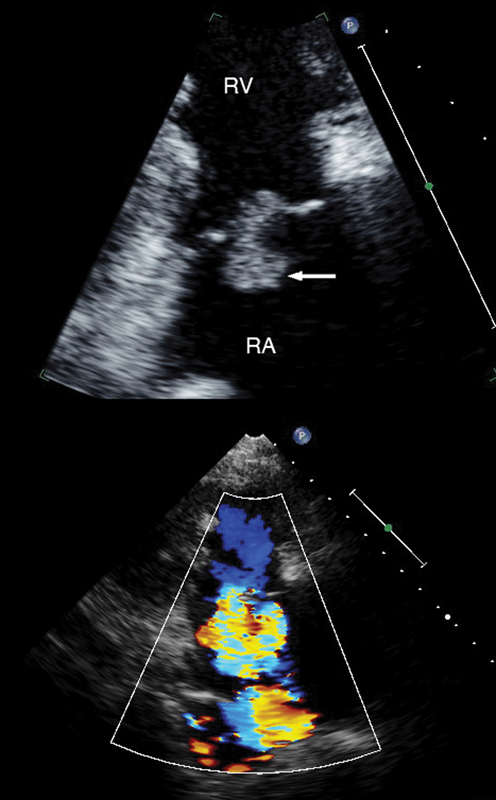

فحوصات تشخيصية لبعض امراض القلب والشرايين التاجية